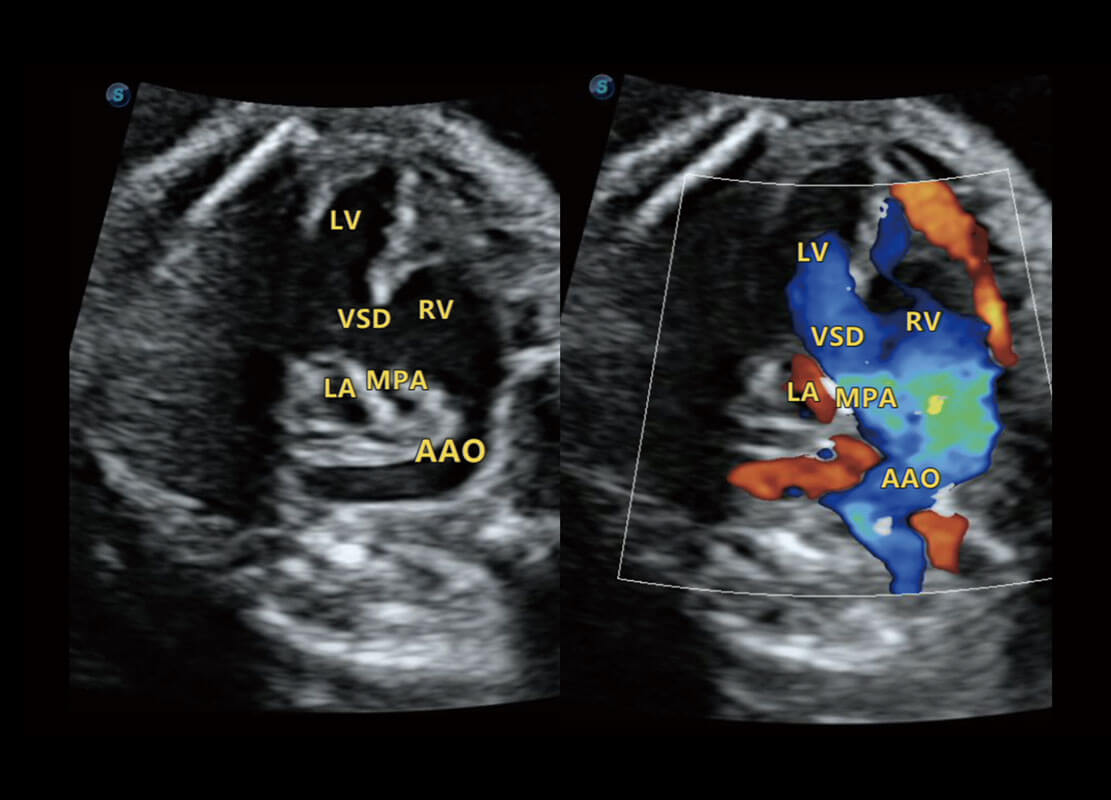

P60搭载一系列胎儿心脏成像技术,实现精细的胎儿心脏评估。

四腔心血流

右室双出口